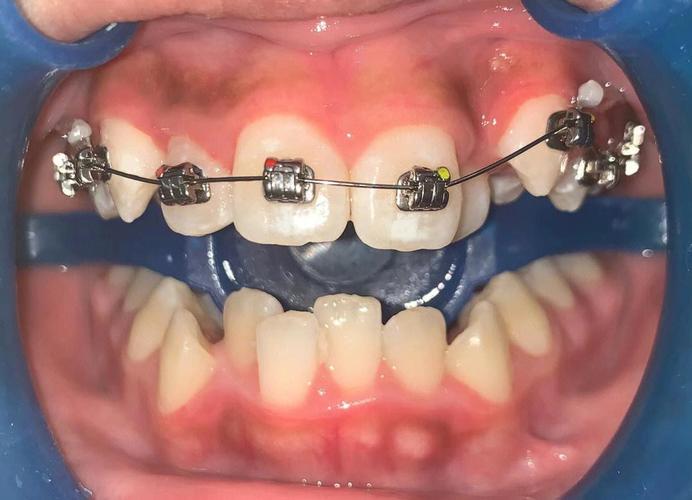

制作与临床应用中,材料选择多为0.016-0.018英寸不锈钢丝,因其弹性模量高,形变后回力稳定,能提供持续的压低力,弯制时需在磨牙区预成水平臂(长度为第一磨牙颊面管至尖牙的距离),前牙区弯制垂直压低曲(曲的弧度需圆滑,避免应力集中),垂直曲顶端与上前牙托槽槽沟底保持1-2mm间隙,确保加力后产生垂直向压力,临床操作时,先将辅弓水平臂插入磨牙颊面管,再用结扎丝将垂直曲与上前牙托槽紧密结扎,辅弓与主弓丝(通常为0.019×0.025英寸不锈钢丝)共同构成力学系统,主弓丝提供支抗,防止后牙伸长,加力周期为4-6周复诊一次,每次调整垂直曲高度0.5-1mm,直至上前牙达到目标位置(如牙冠长度缩短1-2mm,覆合改善II度)。